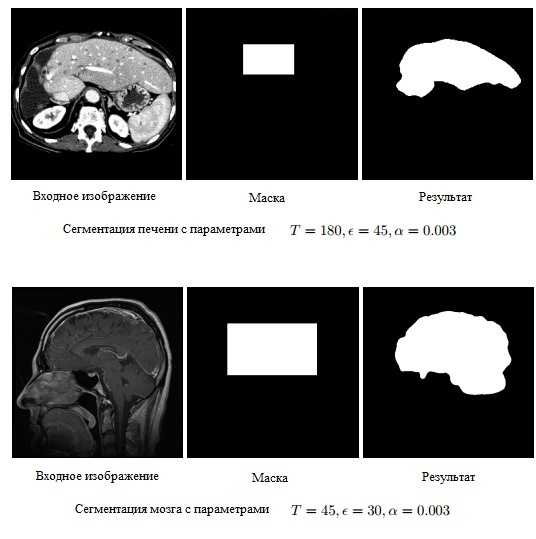

Я проводил тесты алгоритма на двух типах изображений: медицинских и изображений горных пород (так как решал эту задачу на дипломе).

Для медицинских изображений это работает вот так:

Мы видим, что алгоритм очень хорошо справляется с данной задачей.